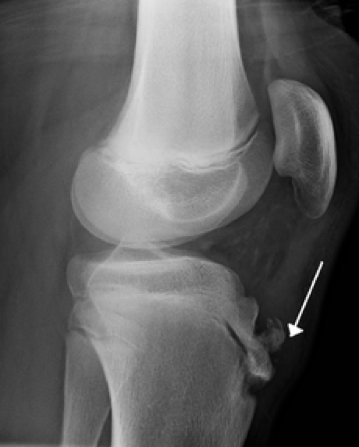

Avulsion fracture

This is an example of an avulsion fracture where there is an injury to the bone in a place where a tendon or ligament attaches to the bone.

When an avulsion fracture occurs, the tendon or ligament pulls off a piece of the bone.

Avulsion fractures are more common in children than adults.